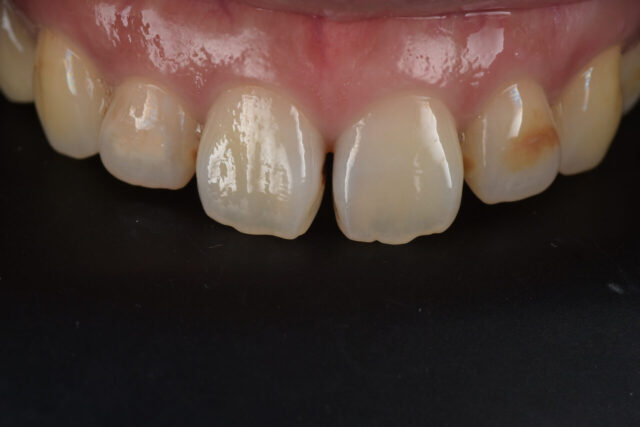

前歯の変色を削らずに改善|ホワイトニング+ダイレクトボンディング症例

before

性別 女性 主訴 「前歯の色が気になる」「できれば削らずにきれいにしたい」というご相談で来院されました。 治療 診査の結果、前歯には失活歯による内部からの変色(いわゆる黒ずみ)が認められました。

通常であれば、ラミネートベニアやセラミッククラウンによる修復が検討されるケースです。

しかし本症例では、歯質の保存を最優先に考え、以下の治療を選択しました。

インターナルブリーチ(ウォーキングブリーチ)による内部漂白

色調改善後にダイレクトボンディングによる形態・色調修正

まず歯の内部に漂白剤を作用させることで、歯質自体の明度を改善。

その後、周囲の歯との色調バランスを考慮しながらコンポジットレジンにて微調整を行いました。

結果として、歯を大きく削ることなく、自然で調和のとれた前歯の審美性を回復することができました。料金 1本10万円+tax 備考 本症例のポイントは、「削らない選択肢」を最大限活かした点にあります。